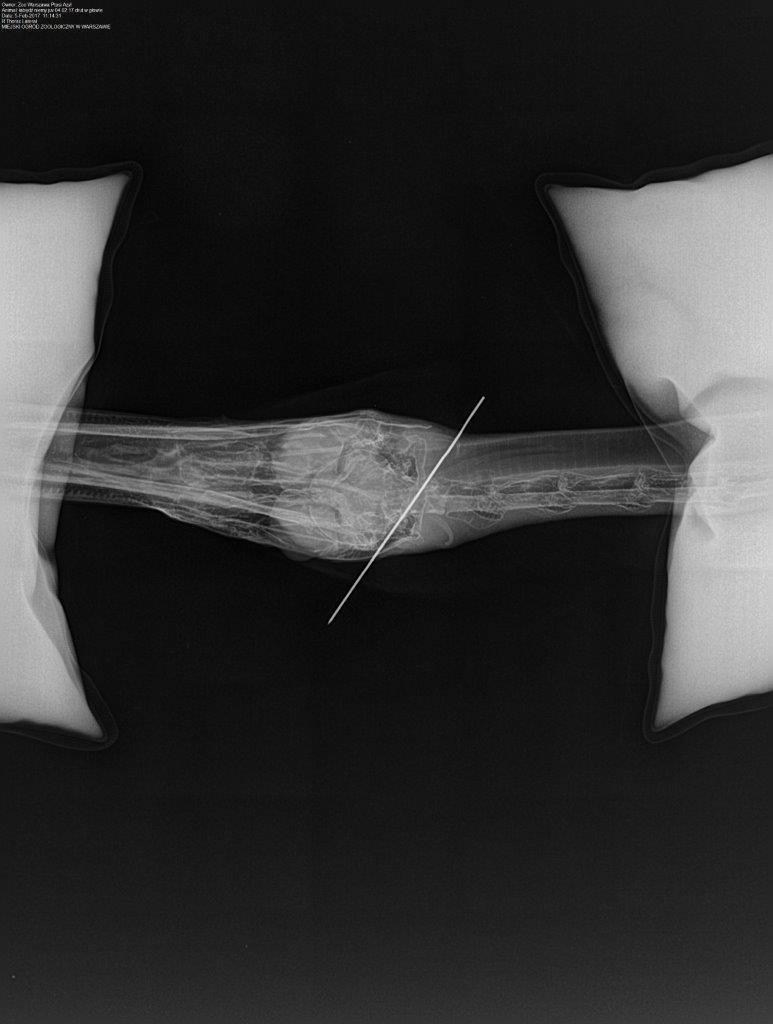

- Fot Facebook/Ptasi Azyl

Dzisiaj w narkozie wykonaliśmy zdjęcia RTG głowy, które na szczęście wykazały to co podejrzewaliśmy – metal utknął w czaszce ale w przestrzeni gdzie znajdują się zatoki, a więc ominął mózg. Kilka minut później usunęliśmy drut a łabędź wybudził się bez większych problemów. Nietypowy pacjent po kilku godzinach dołączył do innych łabędzi.